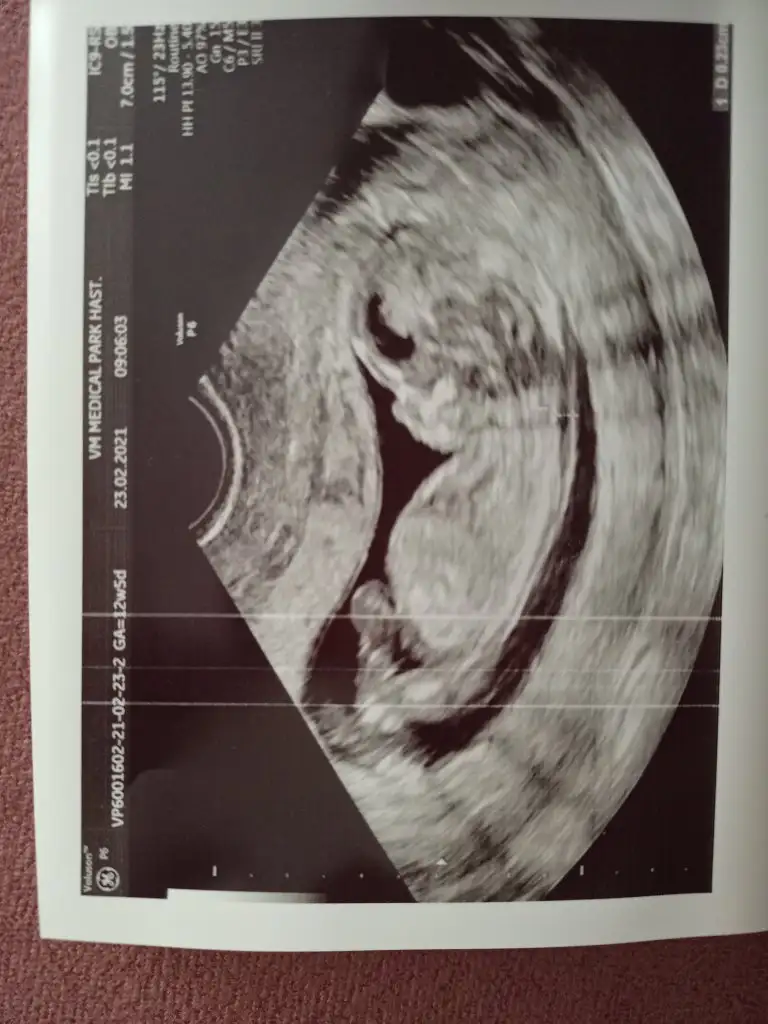

Evet göründü, ölçümünü yaptı 0.31 cm ancak hiç onun hakkında bir şey söylemedi. Çok teşekkür ederim ilginiz için🙏 IMG20210223143857.webp